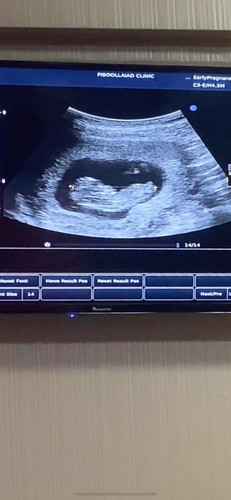

ประมาณกี่ week ค่ะ ไปหาหมอ 3 ที่ตอบไม่ตรงกันสักที่เลย กำหนดคลอดก็คนละเดือน😂 #ท้องแรก

10w3d ประมาณ4.28ซม ค่ะ ไปหา 2 ที่ก็เป็นเหมือนกันหมอกำหนดวันจากขนาดตัวเด็กค่ะ

ของแม่ซาวด์ตอน9w5dค่ะประมาณ3,1ซม